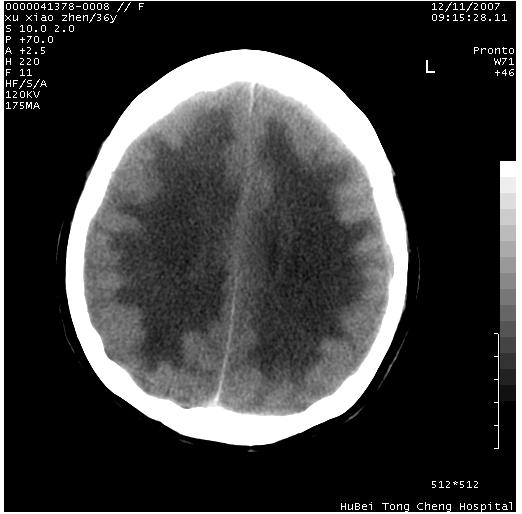

以下是引用wzr在2007-12-12 18:58:00的发言:[br]以脑白质受累,脑肿胀明显,脑室变窄,多考虑炎性改变,建议进一步ce或mri明确.

以下是引用wqs571018在2007-12-12 19:48:00的发言:[br]脑白质受累,脑肿胀明显,脑室变窄,多考虑炎性改变,脑膜炎可能性大;建议mri明确.。